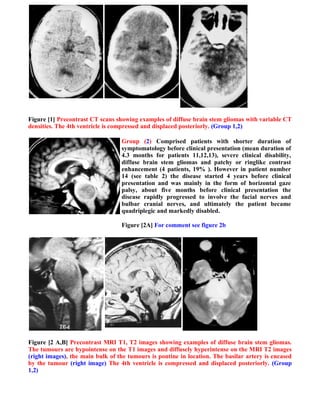

Figure [1] Precontrast CT scans showing examples of diffuse brain stem gliomas with variable CT

densities. The 4th ventricle is compressed and displaced posteriorly. (Group 1,2)

Group (2) Comprised patients with shorter duration of

symptomatology before clinical presentation (mean duration of

4.3 months for patients 11,12,13), severe clinical disability,

diffuse brain stem gliomas and patchy or ringlike contrast

enhancement (4 patients, 19% ). However in patient number

14 (see table 2) the disease started 4 years before clinical

presentation and was mainly in the form of horizontal gaze

palsy, about five months before clinical presentation the

disease rapidly progressed to involve the facial nerves and

bulbar cranial nerves, and ultimately the patient became

quadriplegic and markedly disabled.

Figure [2A] For comment see figure 2b

Figure [2 A,B] Precontrast MRI T1, T2 images showing examples of diffuse brain stem gliomas.

The tumours are hypointense on the T1 images and diffusely hyperintense on the MRI T2 images

(right images), the main bulk of the tumours is pontine in location. The basilar artery is encased

by the tumour (right image) The 4th ventricle is compressed and displaced posteriorly. (Group

1,2)